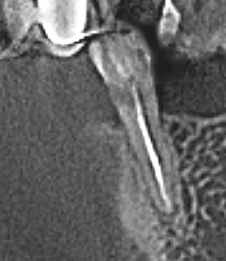

nau_63 Опубликовано 11 ноября, 2025 Поделиться Опубликовано 11 ноября, 2025 (изменено) Добрый день. Задавал вопрос по протезированию этого зуба в разделе Протезирование, но сейчас все идет к установке пломбы, а затем коронки. Поэтому прошу совета здесь. Нижняя 5-ка слева. Сильный клиновидный дефект, очевидно из-за отсутствующего соседнего зуба . Зуб депульпирован и для прочности установлен штифт. Сбоку была пломба, но быстро отвалилась. При надавливании на зуб в сторону языка есть не сильная боль (не понятна причина этой болезненности, зуб пролечен качественно. При жевании даже жесткой пищи чувствительности нет). Клиновидный дефект сильный. Но штифт не просвечивает, т.е. полость менее 50%. Так вот вопрос, каким материалом лучше запломбировать дефект? Увы, но разные врачи предлагают разные варианты. И может быть есть предположение, почему присутствуют болезненные ощущения при одном направлении давления. Изменено 11 ноября, 2025 пользователем nau_63 добавление картинки Ссылка на комментарий

nau_63 Опубликовано 12 ноября, 2025 Автор Поделиться Опубликовано 12 ноября, 2025 (изменено) Добавлю фото. Нижняя часть дефекты немного накрылась десной. Темный фон за зубом - это разрез от установленного 2 дня назад импланта. Изменено 12 ноября, 2025 пользователем nau_63 уточнение Ссылка на комментарий